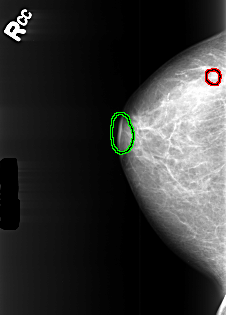

B_3445_1.RIGHT_MLO

RIGHT_CC LINES 4088 PIXELS_PER_LINE 2936 BITS_PER_PIXEL 12 RESOLUTION 50 OVERLAY

RIGHT_MLO LINES 4416 PIXELS_PER_LINE 3056 BITS_PER_PIXEL 12 RESOLUTION 50 OVERLAY

FILE: B_3445_1.RIGHT_MLO.OVERLAY

TOTAL_ABNORMALITIES 2

ABNORMALITY 1

LESION_TYPE MASS SHAPE LYMPH_NODE MARGINS N/A

ASSESSMENT 2

SUBTLETY 3

PATHOLOGY BENIGN_WITHOUT_CALLBACK

TOTAL_OUTLINES 1

BOUNDARY

ABNORMALITY 2

FILE: B_3445_1.RIGHT_CC.OVERLAY

TOTAL_OUTLINES 2